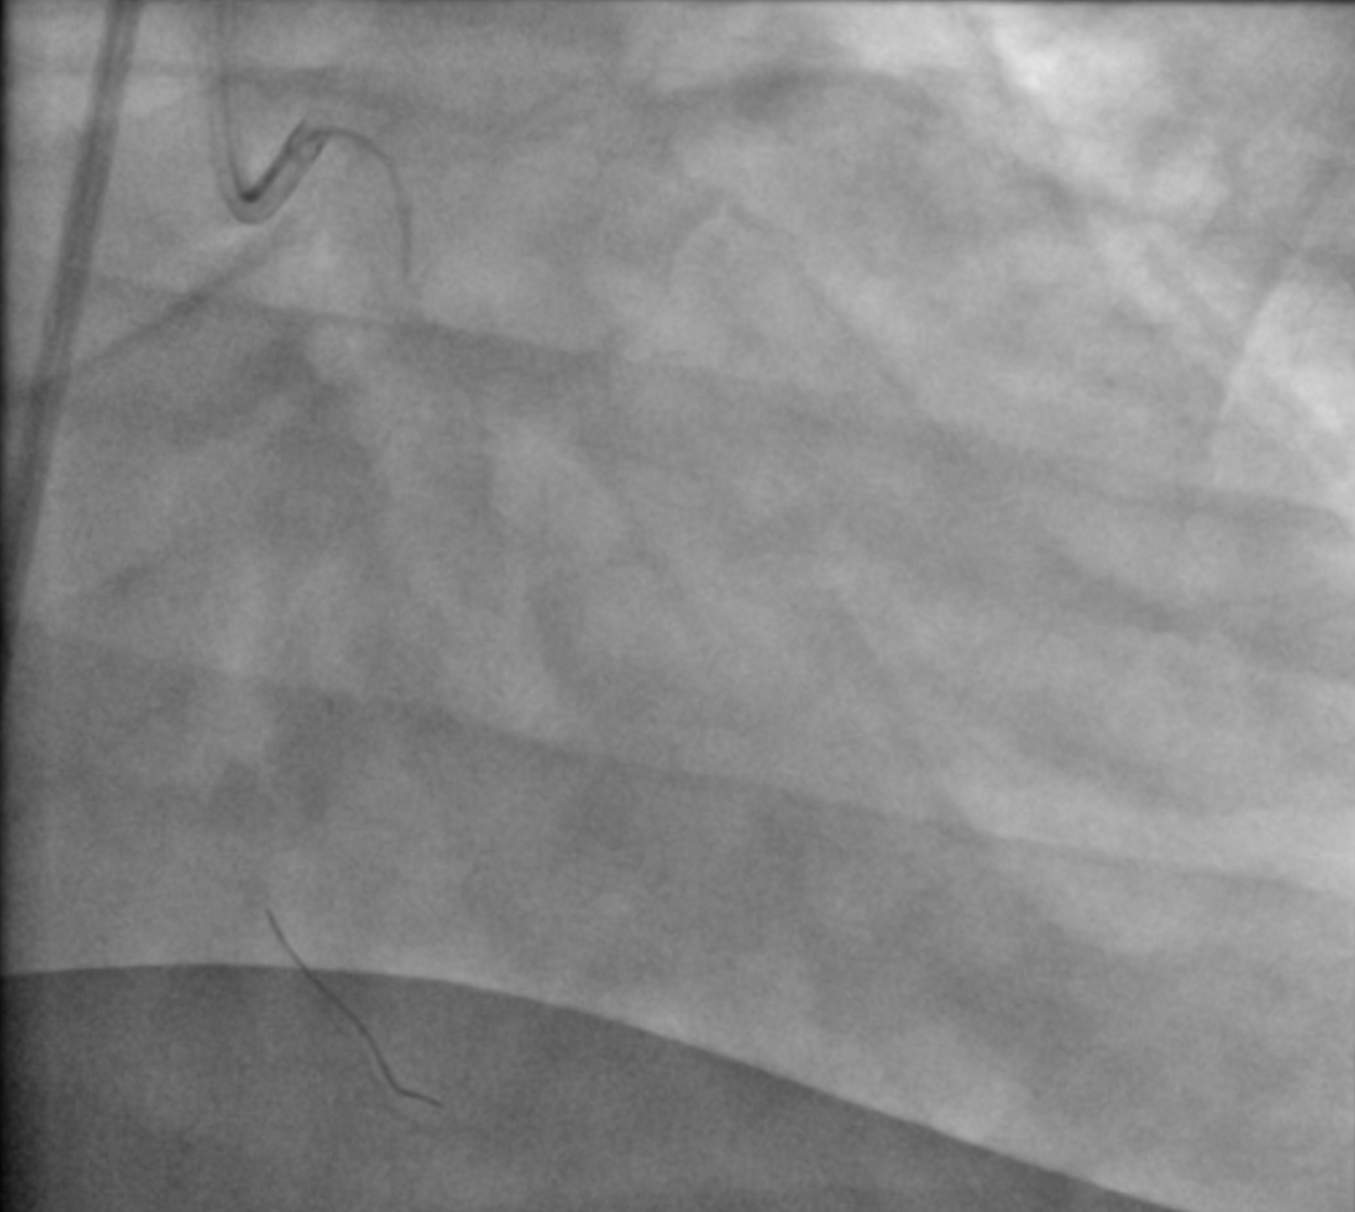

We decided to do orbital atherectomy to ostial LCx and rotational atherectomy to proximal - mid LAD. Calcium debulking was confirmed with IVUS after atherectomy. Subsequent predilation using high pressure scoring balloon in LAD failed to obtain sufficient expansion, hence we decided to use intravascular lithotripsy to further modify the calcium throughout proximal LAD. After obtaining optimal balloon expansion, we proceeded with DK crush to LM-LAD-LCx bifurcation. Dual lumen microcatheter was used to facilitate wire recrossing and ensuring wire would stay in true lumen. After final POT in LM, Repeat IVUS was performed to confirm optimal stent expansion. Suboptimal distal stent landing zone due to diffusely diseased LAD was noted and decision was made to angioplasty the distal LAD with Drug Coated Balloon.

25 final rao cau.mp4